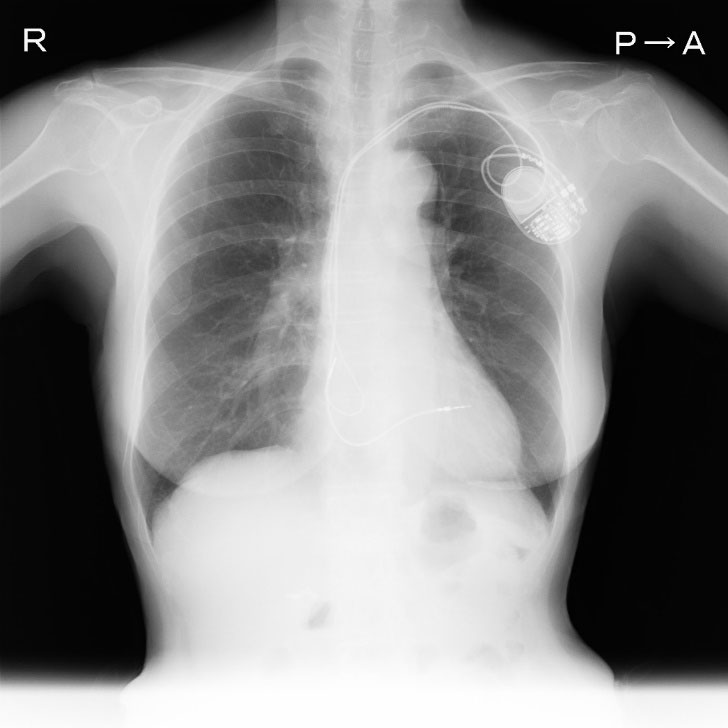

ペースメーカ等の不整脈デバイス治療の手術件数は全国で年間6万件以上が行われており、デバイス治療に関連した合併症も散見され、特に感染を合併した際にはリードを含めたすべての異物除去が必須であることは広く認知されています。

デバイス感染が起きると敗血症や感染性心内膜炎などを起こす恐れもあるため、リードを抜き取る必要があります。リードは植え込まれている年数が長い場合は、静脈や心臓の壁に癒着を起こし牽引しても抜けない状態になります。過度の牽引は血管損傷や穿孔といった致死的な合併症を引き起こす可能性が高く、開胸手術による摘出が行われていました。

エキシマレーザーシースによるリード抜去は、1997年FDAに認可されて以来、欧米にて急速に普及し高い成功率と安全性が報告されており、我が国においても2008年厚生労働省の認可を受け施行可能となり、施設基準があるものの2010年より保険適用となりました。